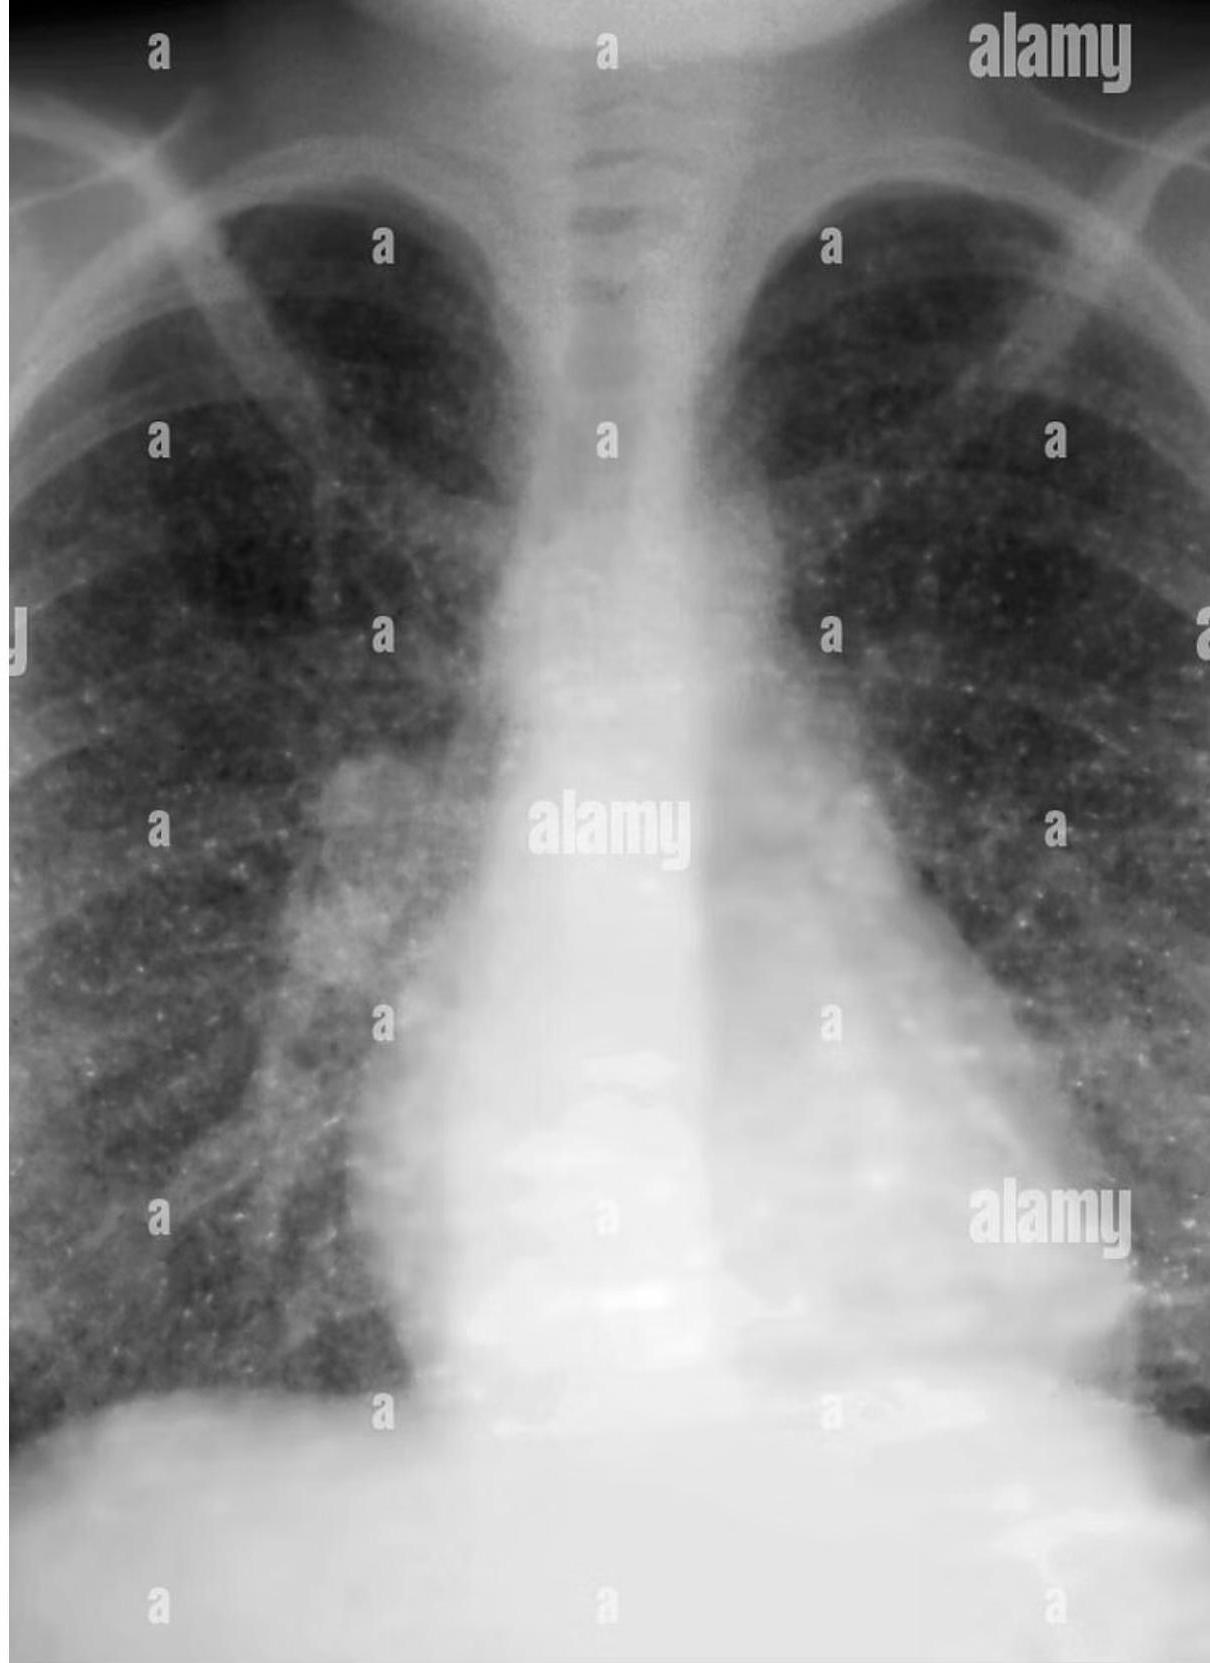

Pediatric chest x-ray showing hilar lymphadenopathy tuberculosis.

Progression Stages

- Ghon Focus: Tuberculoma.

- Ghon Complex: Tuberculoma + Hilar Lymph Node Adenopathy (Not visible without calcification).

- Ranke Complex: Visible calcified complex.

- Hilar/Mediastinal Adenopathy: Most common abnormal finding; often the only visible abnormality in early disease.

Radiography is cornerstone for diagnosis in children due to clinically silent presentations. All lobar segments equally at risk for initial infection. • 25% of cases involve two or more lobes • Hilar lymphadenopathy inevitably present • Partial bronchial obstruction causes air trapping • Progressive destruction leads to cavitation